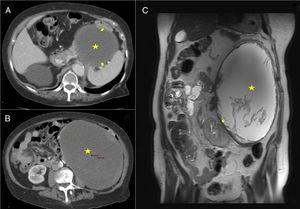

A y B) TC: tumoración quística (marcada con estrella) que comprime y desplaza bazo, colon y riñón izquierdo (flechas). C) RM-T2: tumoración con contenido líquido y material interno heterogéneo (marcada con estrella), las paredes presentan una morfología irregular y un calibre aumentado, desplaza inferior e internamente el riñón izquierdo (flecha).

Se presenta el caso de una paciente de 84 años, con historia de dolor lumbar irradiado a flanco e hipogastrio, asociado a masa abdominal palpable de 8años de evolución que ha ido aumentando de tamaño. A la exploración física el abdomen es blando, depresible, objetivándose una masa en hemiabdomen izquierdo que se extiende desde región subcostal hasta fosa ilíaca izquierda, de bordes lisos, no dolorosa a la palpación. Tanto el hemograma, la bioquímica y las pruebas funcionales hormonales no mostraban alteraciones reseñables. Se realizó tomografía computarizada (TC) visualizándose gran masa en hemiabdomen izquierdo, caudal y medial al ángulo esplénico del colon, predominantemente quística, de 20x14,5x19,5cm (fig. 1A y B). Se realizó resonancia magnética (RM) destacando gran masa retroperitoneal que ocupa todo el flanco izquierdo, de contenido líquido (fig. 1C), sin poder precisar su origen. Dado el gran tamaño de la tumoración, la sintomatología y la necesidad de filiarla, se decide realizar intervención quirúrgica. Se realizó laparotomía media visualizándose una tumoración quística gigante intraabdominal de aproximadamente 20x15x15cm (fig. 2A). Se efectuó resección completa sin presentar complicaciones. La paciente presenta un postoperatorio satisfactorio siendo dada de alta al quinto día postoperatorio. En la revisión en consulta la paciente se encuentra asintomática y tras 12 meses de seguimiento no hay signos de recidiva. El informe anatomopatológico determinó que se trataba de un adenoma suprarrenal gigante con degeneración quística secundaria a hemorragia con necrosis fibrinoide (fig. 2B).